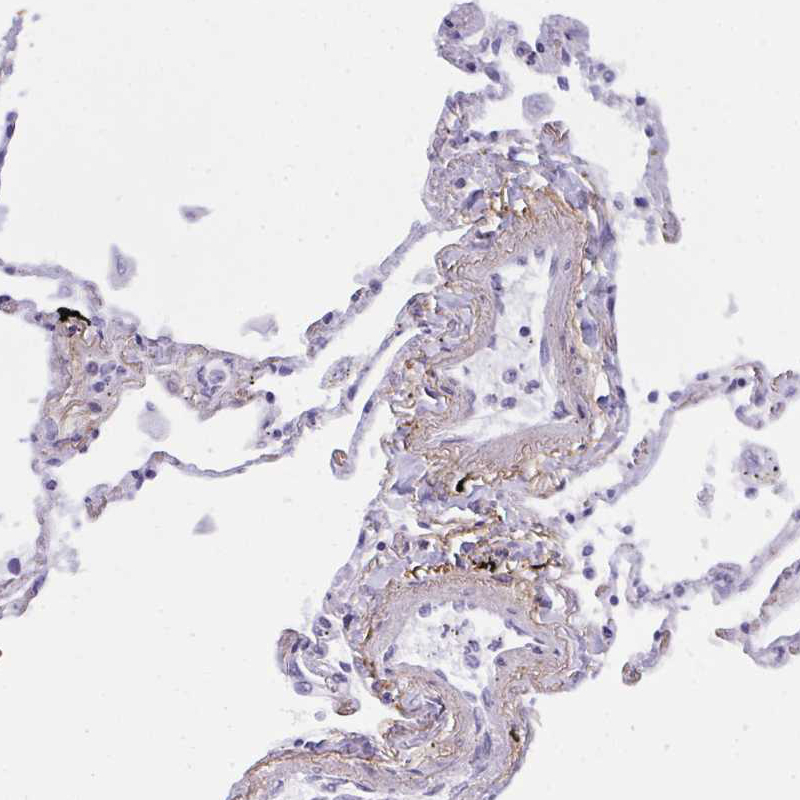

Immunohistochemical staining of human lung shows moderate positivity in the extracellular matrix in blood vessels.